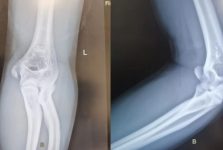

小儿骨科

科室介绍

山东大学齐鲁医院青岛院区小儿骨科,科室成员组成有3名副主任医师,主治医师2人,住院医师1人,其中硕士2人,科室成员都有多年的工作经验,多人分别到北京积水潭医院,上海新华医院,天津医院学习小儿骨科,分别师从于国内著名的小儿骨科专... 查看更多